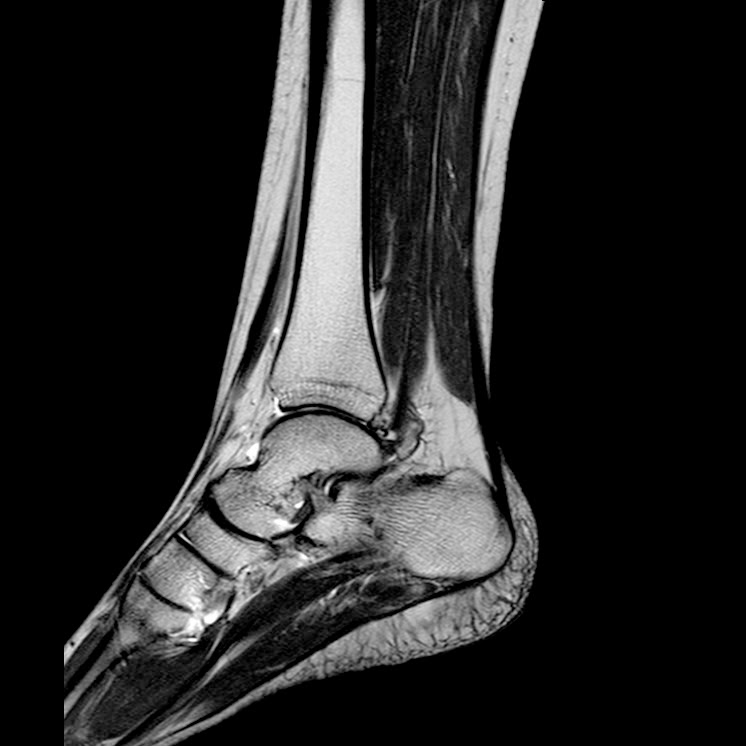

Caso interesante #3

Paciente 1 (Caso de referencia)

Masculino 17 años

Caso interesante # 3